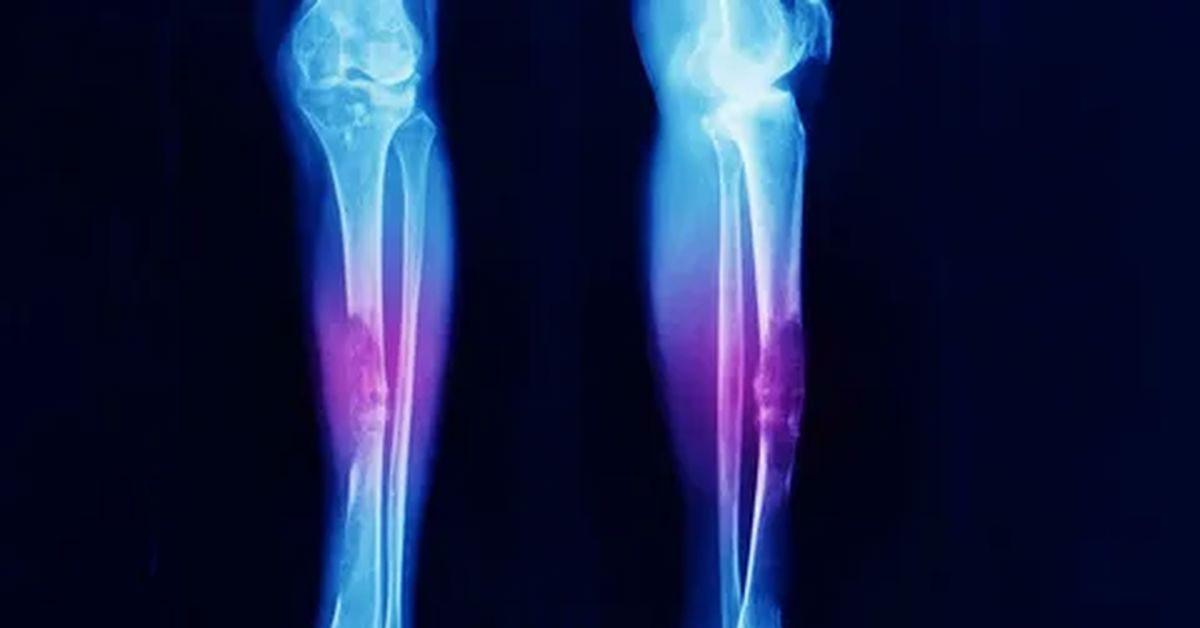

Vücudumuzdaki kas, yağ, sinir, bağ dokusu, tendon veya damar gibi yumuşak dokularda oluşan anormal hücre çoğalmalarıdır. Yumuşak doku tümörü nedir? sorusunun en temel yanıtı; vücudun farklı bölgelerinde iyi huylu veya kötü huylu kitleleri ifade etmesidir. Bu tümörler vücudun hemen her bölgesinde ortaya çıkabilir. Çoğu zaman iyi huyludur ve yavaş büyür. Ancak bazı durumlarda kötü huylu (malign) tümörler de gelişebilir ve bu tür tümörlerin erken fark edilmesi büyük önem taşır.

Yumuşak doku tümörleri, kas, yağ, sinir, damar ve bağ dokusu gibi vücudun yumuşak yapılarında oluşan kitlelerdir. Bu tümörler iyi huylu olabileceği gibi bazı durumlarda kötü huylu da olabilir. Vücudun hemen her bölgesinde gelişebilirler ve çoğu zaman uzun süre belirti vermeden büyürler.